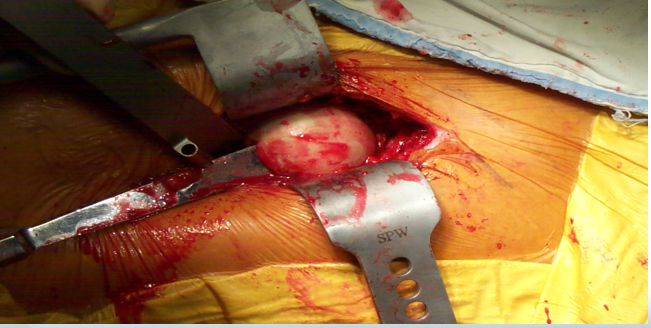

股骨颈截骨下肢内收、后伸 、外旋后取出股骨头

准备髋臼

置入假体